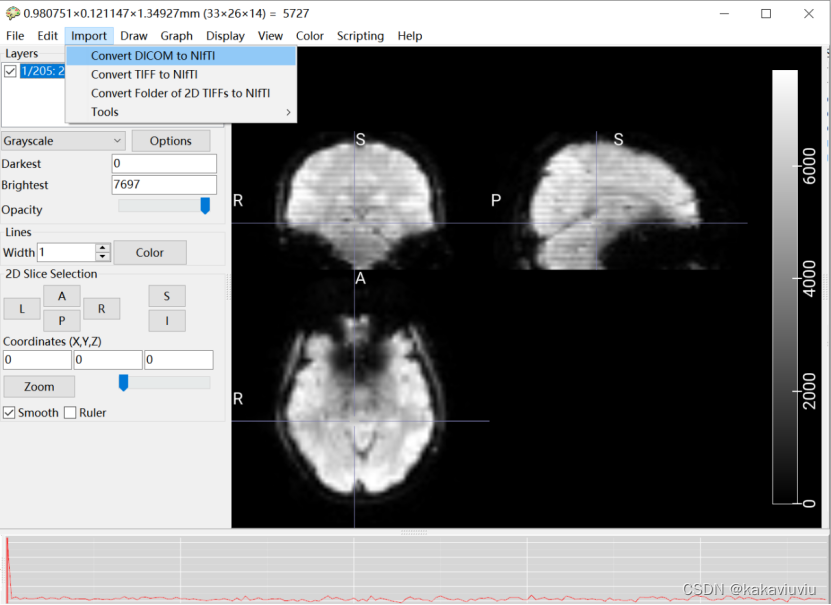

或者使用microGL(既可看图又可转换文件)